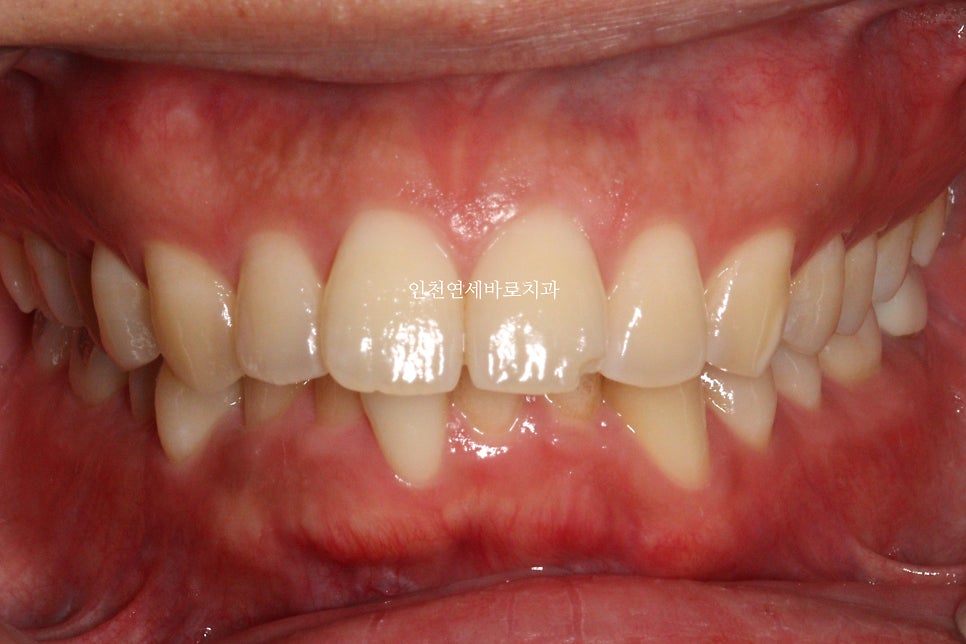

치료 전과 후의 비교입니다.

교합도 양호하게 마무리.

인비절라인은 교합이 맞지 않는다? 라는 말은 가스라이팅 당하신겁니다.

악궁의 확장을 통한 앞니의 후방이동도 최대한 이루어냈습니다.

인비절라인으로 과개교합 치료가 가능합니다. 다만 치료 난이도가 높아 전문적인 노하우와 경험이 필요합니다. 이 사례에서는 1회 재제작을 통해 약 1년간의 치료 기간으로 과개교합과 뻗친 앞니를 성공적으로 교정했습니다.

인비절라인으로도 정확한 교합 조정이 가능합니다. 이 사례에서 보듯이 치료 후 교합이 양호하게 마무리되었습니다. 교합을 정확히 맞추기 위해서는 전문적인 치료 계획과 노하우가 필요합니다.

이 사례처럼 악궁 확장을 통한 앞니의 후방이동으로 발치 없이 치료가 가능한 경우가 있습니다. 다만 개별 케이스에 따라 치료 방법이 달라지므로 정밀 진단을 통해 치료 계획을 수립해야 합니다.